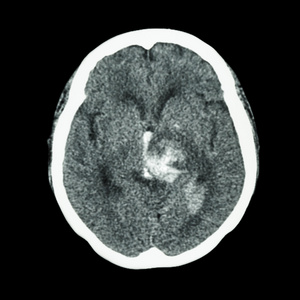

ct影像,多为脑动脉瘤破裂出血血一一一一一神经血管外科赵千山主任